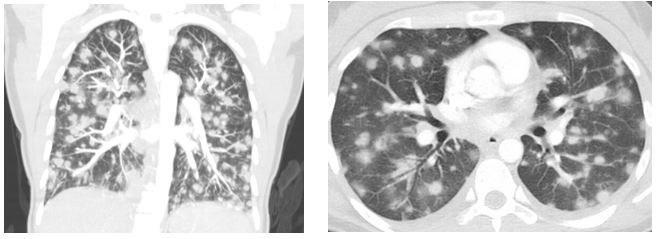

antinuclear cytoplasmic antibodies (ANCA). Representative CT scan images

of the chest are shown below (Figure 1).

Figure 1